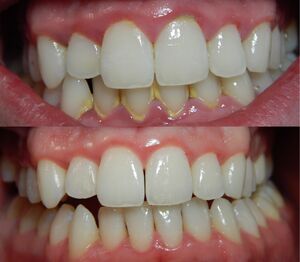

حالة التهاب لثة حادة. | |

التهاب اللثة (إنگليزية: Gingivitis)، هو هو مرض غير مدمر يسبب التهاب في اللثة.[1] الشكل الأكثر شيوعًا من التهاب اللثة، والشكل الأكثر شيوعاً من أمراض دواعم الأسنان بشكل عام، هو الاستجابة لبكتريا الأغشية الحيوية (وتسمى أيضًا اللوحة السنية أو البلاك) التي تعلق على أسطح الأسنان، يطلق عليه "التهاب اللثة الناجم عن البلاك". تحدث معظم أشكال التهاب اللثة بسبب البلاك.[2]

يمكن علاج التهاب اللثة بالاهتمام بنظافة الفح؛ ومع ذلك، فبدون علاج، يمكن أن يتطور التهاب اللثة إلى التهاب دواعم السن، حيث يؤدي التهاب اللثة إلى تدمير الأنسجة والارتشاف العظمي حول الأسنان. يمكن أن يؤدي التهاب دواعم السن في النهاية إلى فقدان الأسنان.[5]

يكون مسبب أمراض اللثة هو بكتيريا البلاك التي تتراكم على الأسنان وحولها وبينها. إذا لم تزال هذه البكتيريا بانتظام بتنظيف الأسنان بالفرشاة أو خيط تنظيف الأسنان، فيؤدي ذالك إلى تهيج اللثة، ومن ثم احمرارها وتورمها ونزيفها، وهذه جميعها أولى أعراض الإصابة بأمراض اللثة، التي تسمى التهاب اللثة.

إذا لم يتم علاج هذه الأعراض التى تكون في الاصل خاصة بأمراض اللثة، قد تظهر جيوب صغيرة بين الأسنان واللثة. ازدياد عمق هذه الجيوب قد يؤدي في النهاية إلى الإصابة بالتهاب الأنسجة الداعمة، وهي أحد أكثر أنواع أمراض اللثة خطورة. وبمجرد الوصول إلى هذه المرحلة من أمراض اللثة، قد يكون الضرر حدث بالفعل، وسيؤدي عدم علاج هذه الحالة إلى فقدان الأسنان. ولهذا السبب، من المهم جدًا العثور على علاج فعال لأمراض اللثة في المراحل المبكرة لالتهاب اللثة، لنحافظ على صحة اللثة ومنع فقدان الأسنان.